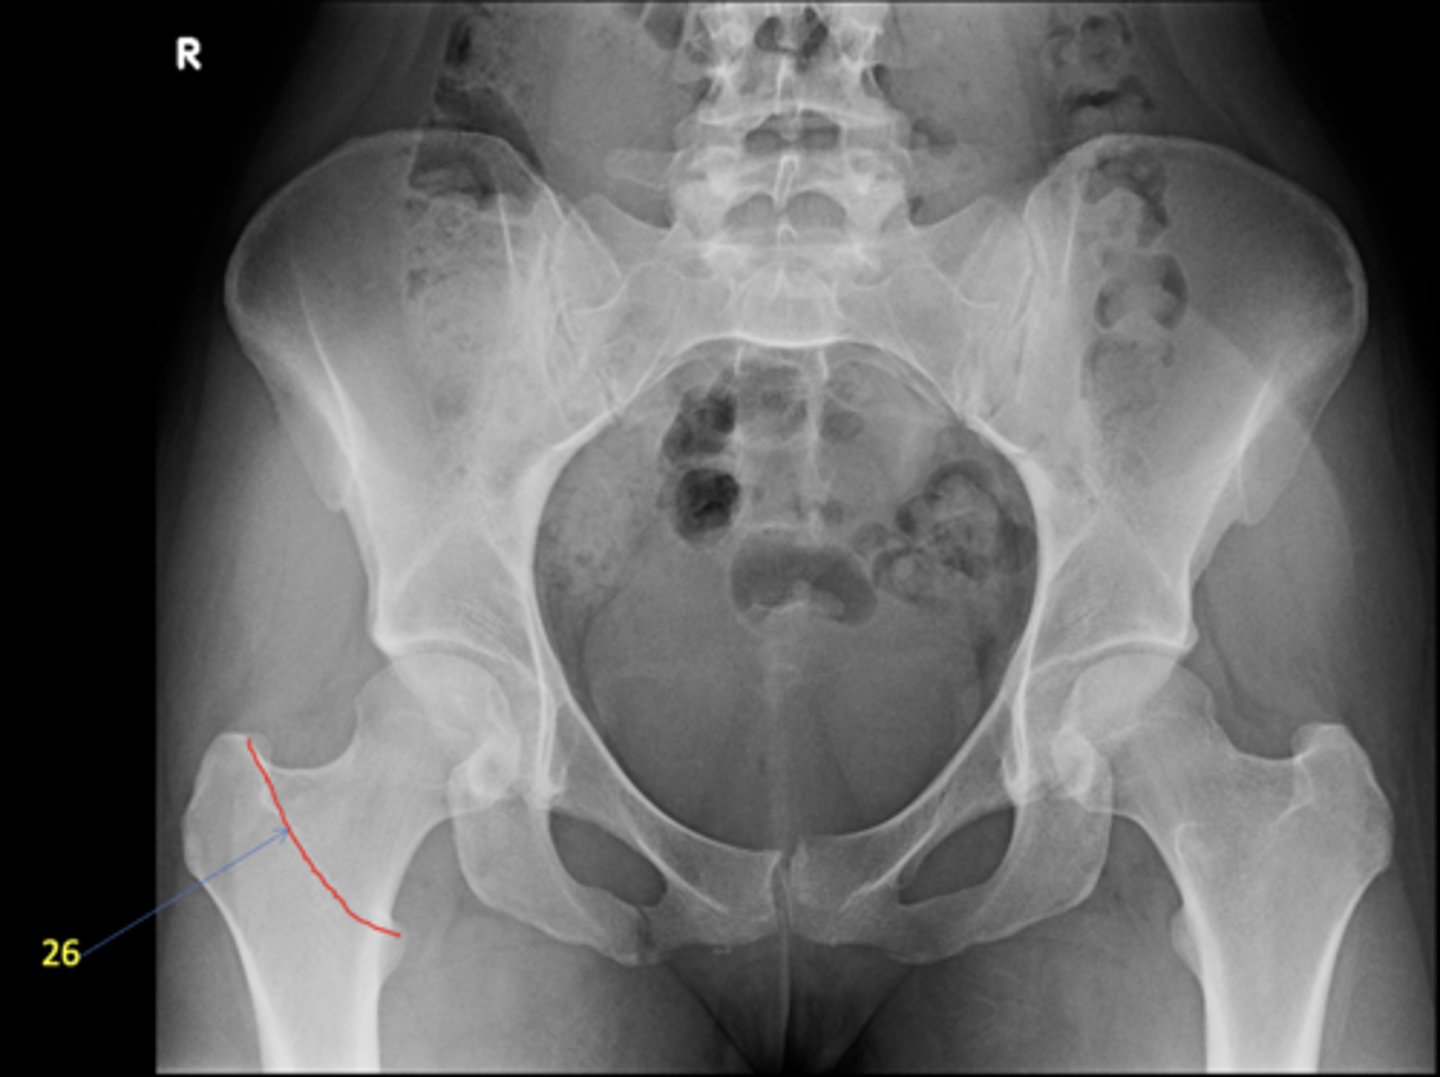

1

AP pelvis

23

Right intertrochanteric crest

ID 26